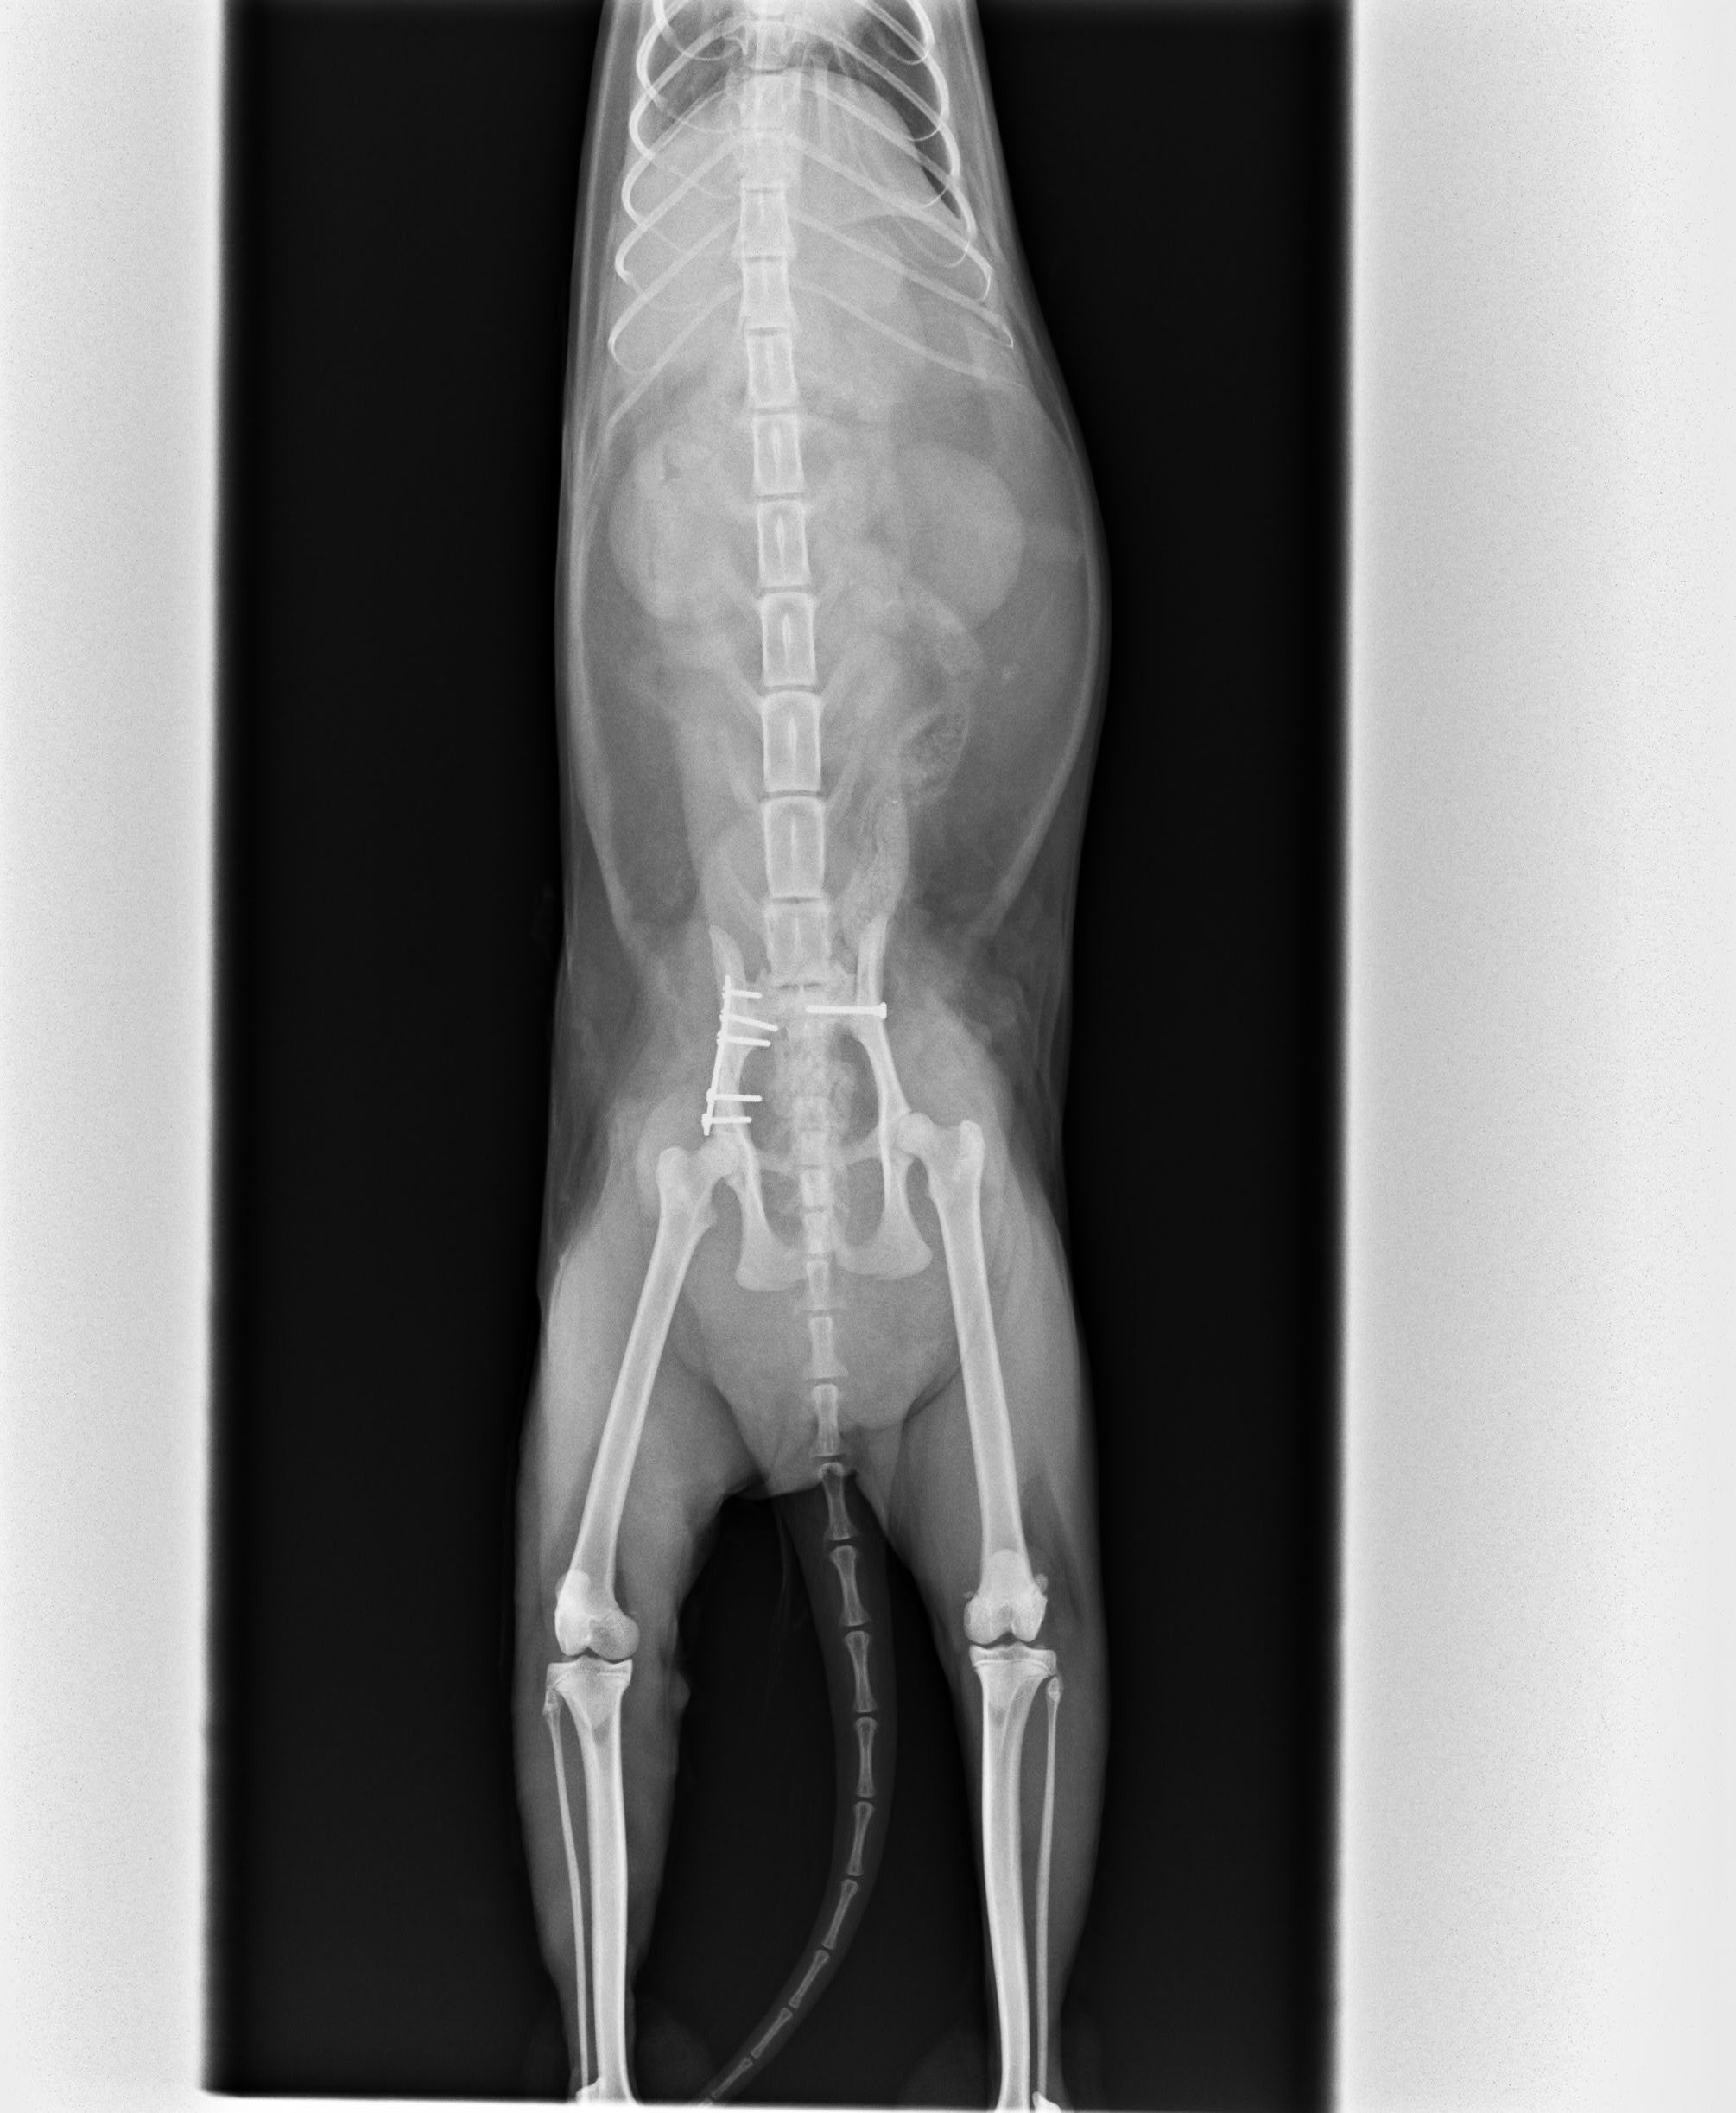

主題: 車禍骨折的三花貓 申請者姓名: 黃儀芬 花色: 申請日期: 2013-04-19 12:50:53 申請者部落格: 申請者臉書網址: 所在縣市/合作醫院: 台北市/其他院所醫助專案(醫院請先MAIL溝通) 治療費用: 20000元 需求人數: 41人 已結案 (2013-06-27 14:24:14) 報名人員: Ocean x2(已付款)、茶咪(已付款)、茶咪、Irene Chen x2(已付款)、Yu Chung(已付款)、茶咪、lavinia(已付款)、小筑Q醬 x2(已付款)、vivian(已付款)、洪嘉淑 x2(已付款)、張湘婷、謝小欣(已付款)、Hllen Liu(已付款)、beforn x4(已付款)、p.p(已付款)、Amy Chou x2(已付款)、Kim Meng(已付款)、Jessica Hsu(已付款)、Kate(已付款)、林紫翠 x2(已付款)、小豬(已付款)、Emily Chou x10(已付款)、Sunny Chen(已付款)、Den Miyako x2(已付款)、Sandy Shen(已付款)、 候補人員: 動物病情說明: 3/14貓咪被發現在我們店後面的紙箱堆中,疑似遭到車禍撞擊緊急送醫。3/14晚間先安排貓咪住院穩定其生命跡象,3/15再送往醫師建議的美國愛屋動物醫院。

由於骨折及神經修復有時效性,故安排於3/16動手術。

我們有請醫院開立估價單,原價為72600~72800,但因為是浪浪救援,醫院為我們打折,手術加住院總金額為4萬元整。可是還是超過了我們所能負擔的範圍.....希望能透過協會的力量幫我們湊齊不足的醫藥費用....動物近況說明: 貓咪由原本需要醫師幫忙擠尿擠便進步到可以自行如廁,左後腿恢復良好,右後腿小腿以下無明顯反應走路腳掌會拖行,目前持續復健中。